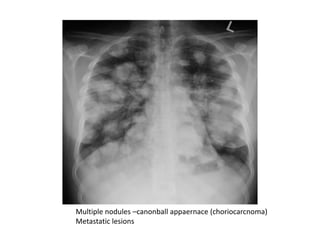

Cannon ball lesions:Multiple nodules, widely disseminated,usually

multiple, clearly demarcated 1- 2cm in diameter circular shadows

throughout the lung fields (characteristic of secondary deposits)

Multiple nodules –canonball appaernace (choriocarcnoma)

Metastatic lesions